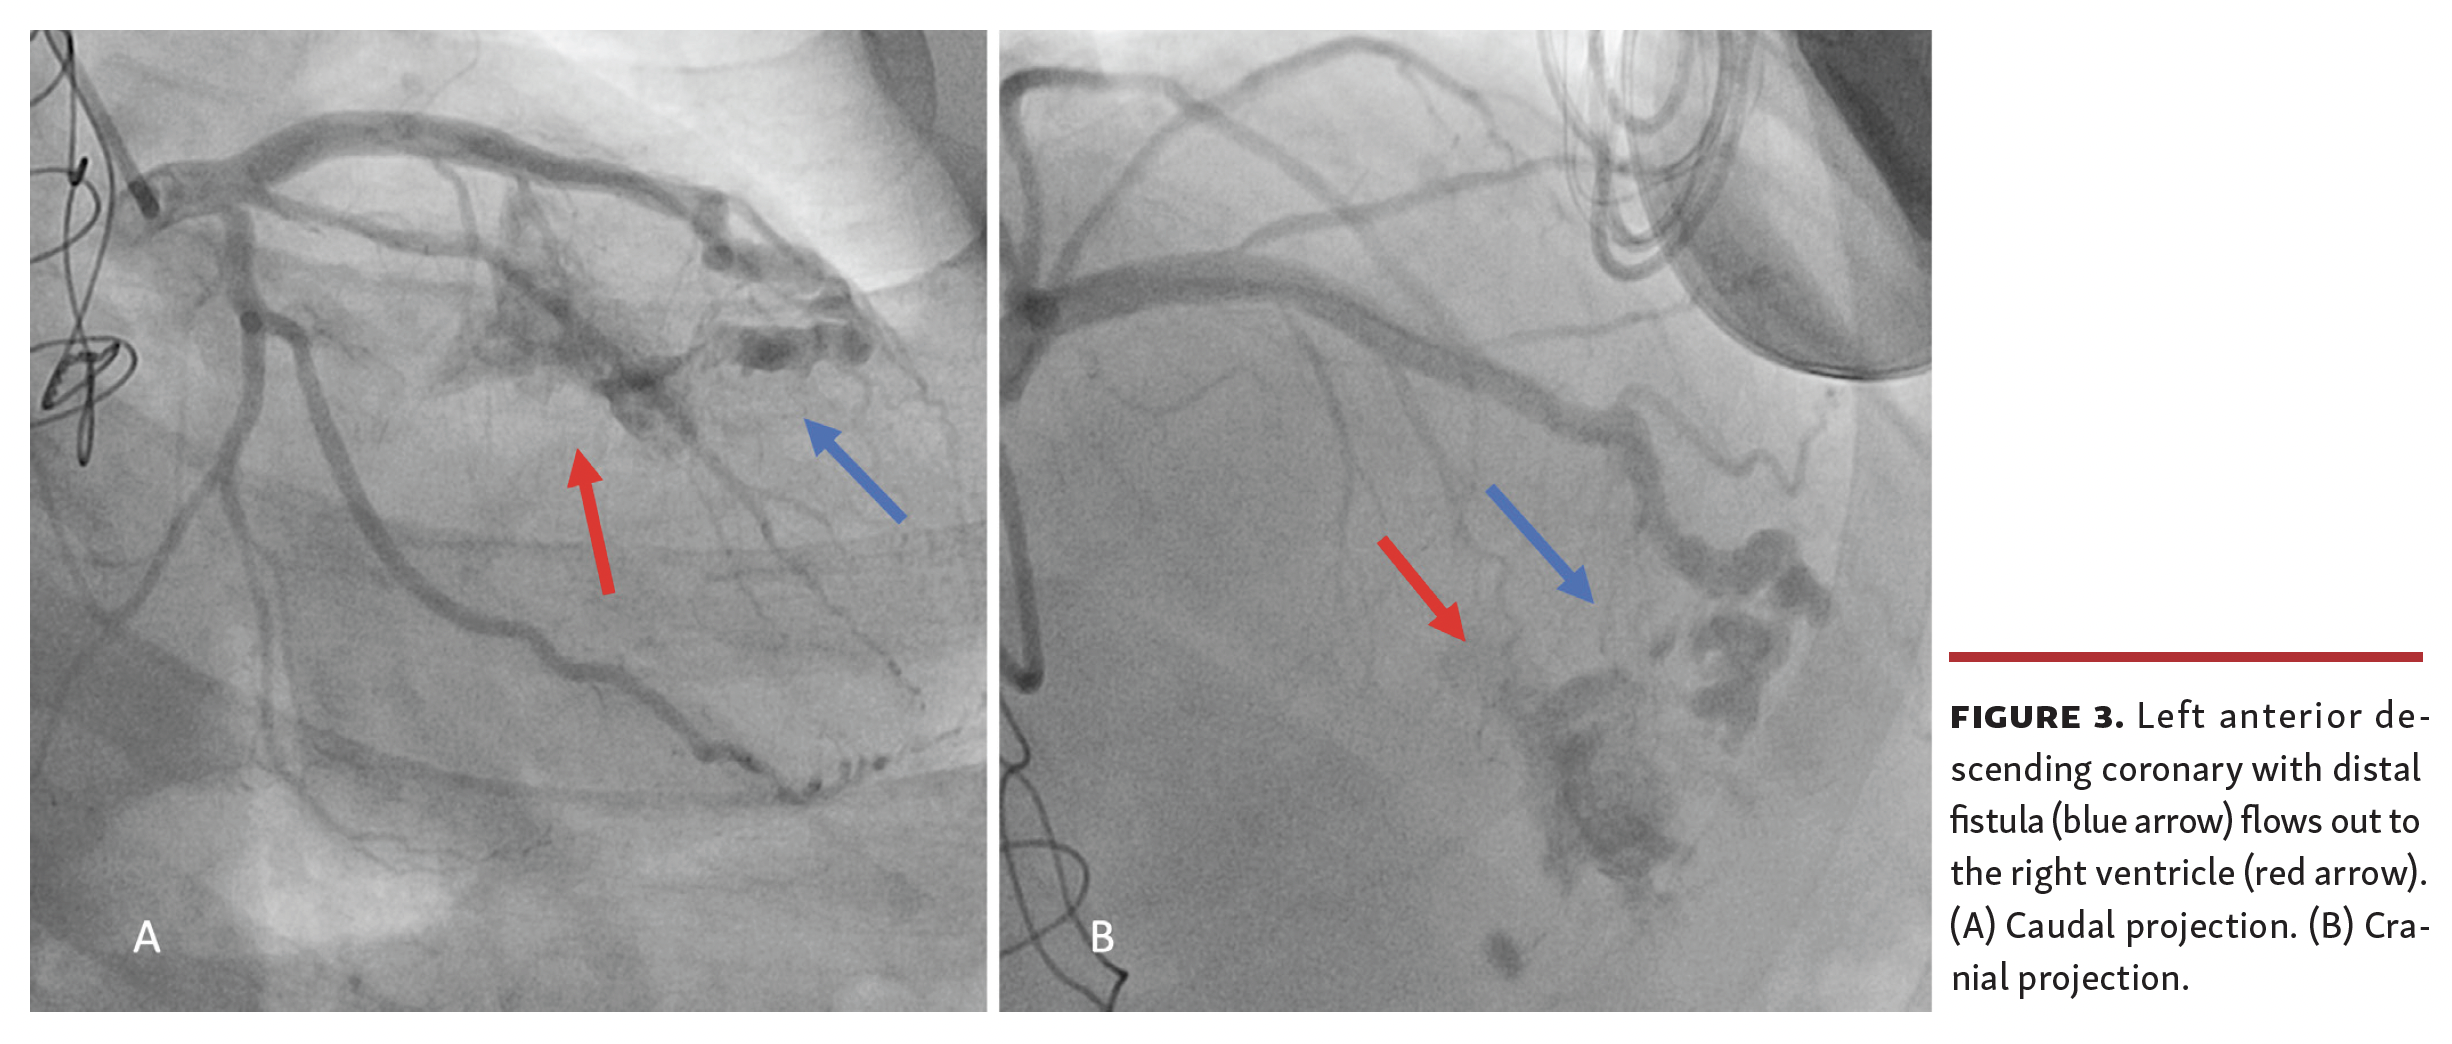

Coronary angiography was performed and displayed a fistula between the left anterior descending artery and right ventricle with subsequent coronary occlusion (Figure 3 and Video 1). This is a rare, albeit reported, complication of endomyocardial biopsy.